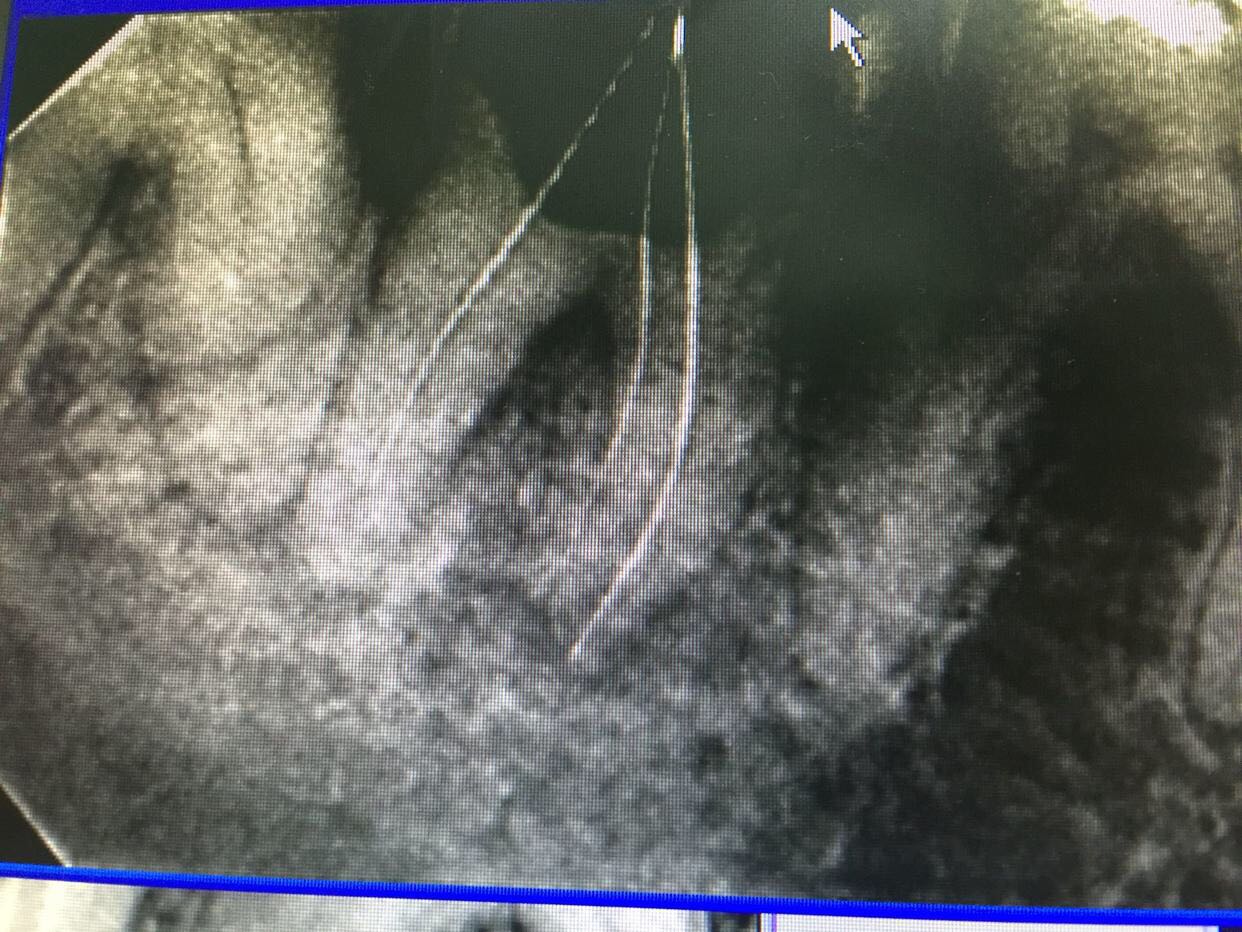

检查:47颊合面深龋,探及穿髓,探痛无,牙龈未见明显红肿,冷诊(-)。X线片示:47根尖区低密度影像。

诊断:47慢性根尖周炎 治疗:47去龋净,开髓揭顶全,拔髓,疏通根管,测长,根管预备,冲洗,干燥,试尖,根管封药,告医嘱,肿痛随意。